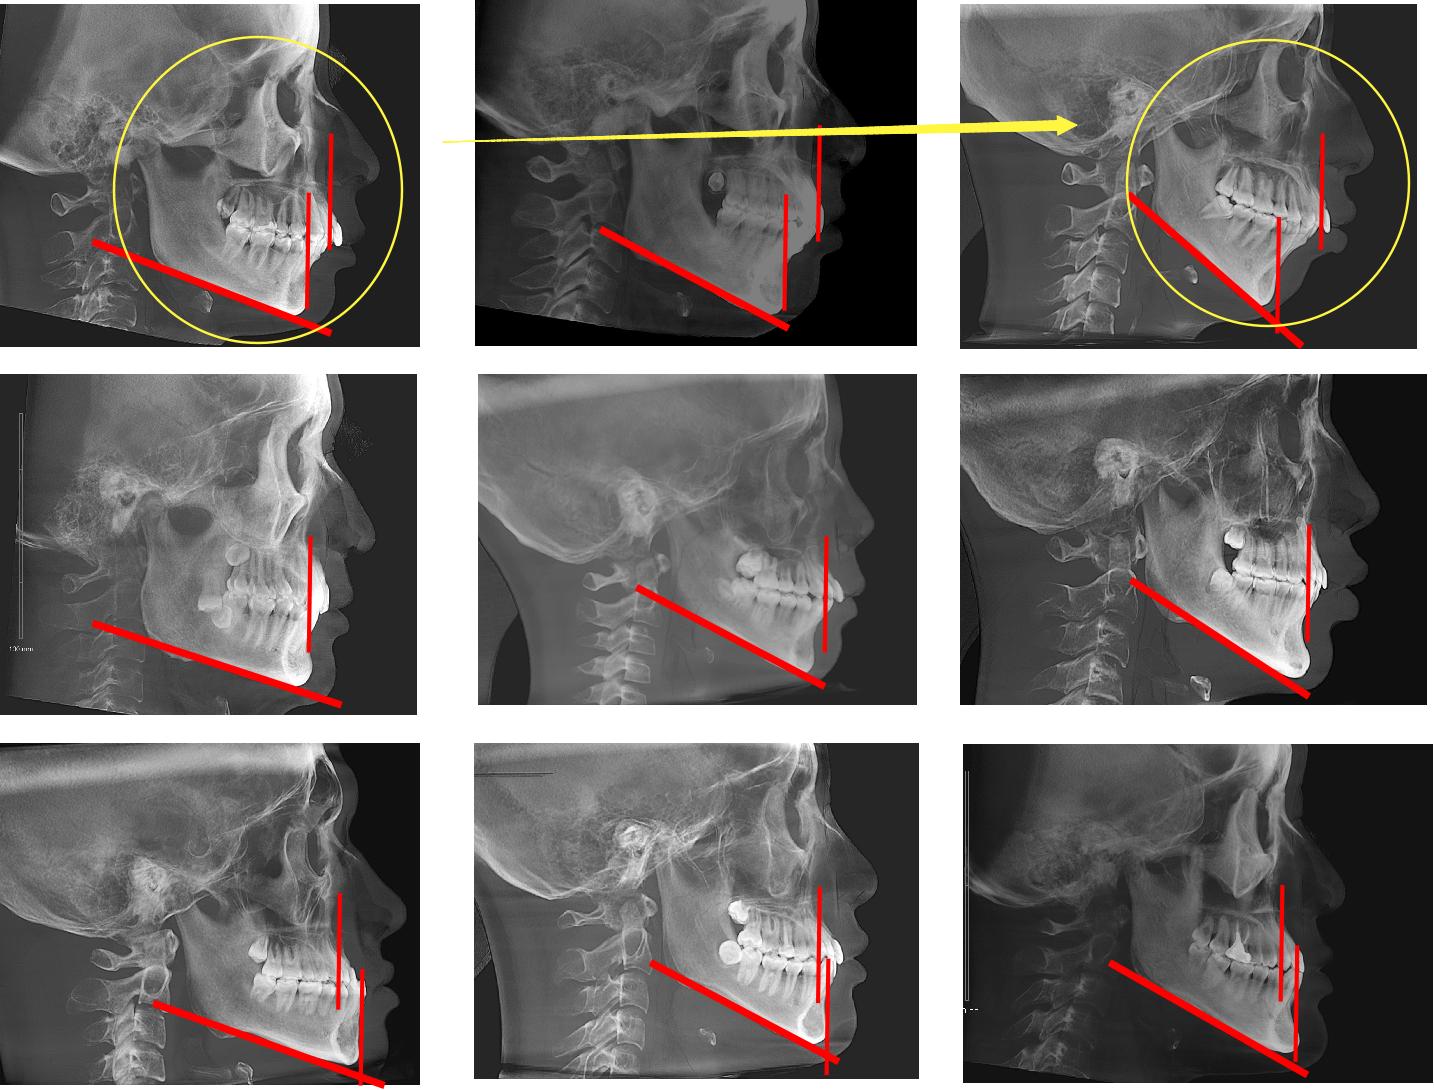

很明显,花花是低角型。看一下面部比例,从眉间点到鼻下的距离基本等于鼻下到颏下的距离,这就是非常和谐的面型。

伴有轻微下颌后缩,但是颏部发育马马虎虎,这个侧面就不太有颏部的形态。

但是

突然就变成了一个高角型。而且看一下面部比例,从眉间点到鼻下的距离小于鼻下到颏下的距离。这个面部比例变得不协调,看起来就是嘴要很努力才能闭上的感觉。

下颌后缩伴高角型的人,会有两个经常性的表现:一个是开唇露齿,一个是当嘴唇闭紧是颏肌紧张。

所以花花是从这个状态变到了这个状态:(黄色圈圈和箭头)

从一个本来有些下颌后缩的低角型变成了一个下颌更加后缩的高角型。